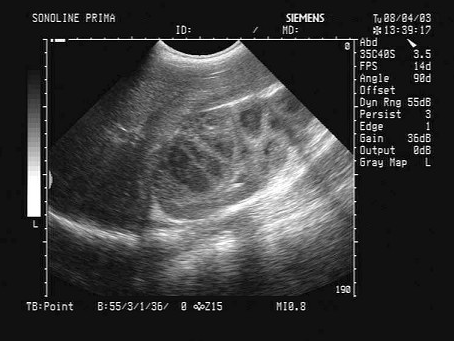

7、单项选择题

某患者左肾超声声像图如下,最可能的诊断为()。

A.多发性肾囊肿

B.肾结核

C.多囊肾

D.重度肾积水

E.中度肾积水

点击查看答案